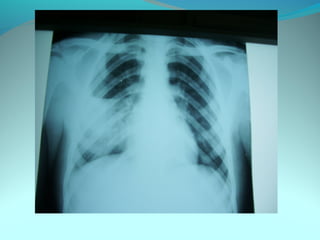

Opacité occupant la partie externe du 1/3 infer du poumon droit

dense et homogene ovalaire de 8cm de grand axe vertical

La limite externe se confend avec une opacité d’environ 1cm comble

les coupole costodiaphragmatique droit

Limitée a sa partie sup par la petit sessure qui est epaisse et pas de

lyse costale

 DIAGNOSTIC :DIAGNOSTIC :

 1_1_cancer bronchique droit( d epaississement)

 2_2_ kyste hydatique au stade sain